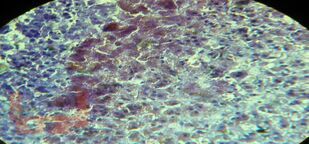

В учебном пособии «Патологическая анатомия критических состояний» на современном уровне изложена актуальность изучения клинической патологической анатомии. Освещены принципы современной патоморфологической диагностики, основы работы с нормативной документацией, принципы построения патологоанатомического диагноза, что заложено в освоении современных общепрофессиональных и профессиональных компетенций в подготовке врача. Приведенные клинические примеры посмертной патоморфологической диагностики с описанием гистопрепаратов, обозначением структурных изменений, оформлением образцов нормативной документации делают информацию более доступной и запоминающейся, формируя основы клинического мышления и клинико-анатомического анализа на особенностях патоморфогенеза заболеваний, что заложено в основе российской патологоанатомической школы.